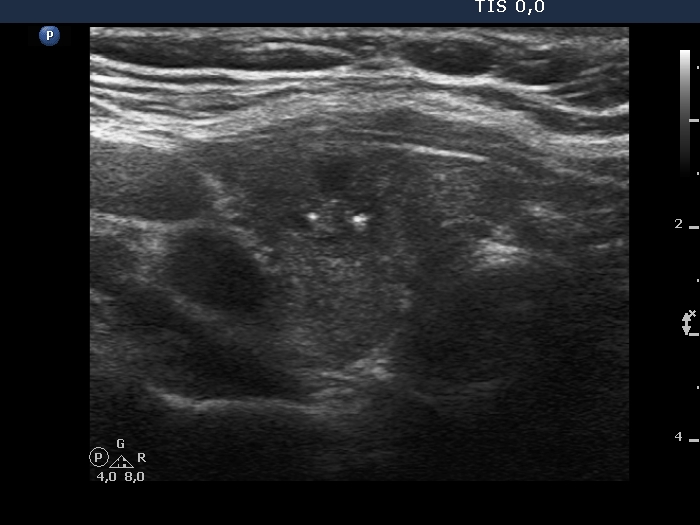

Examination in 2018 (second row of images):

Clinical data. The patient came to a routine follow-up. She had no complaints.

Palpation: unchanged.

Laboratory test: TSH 0.36 mIU/L on daily 125 microgram levothyroxine.

Ultrasonography. Except for the lesion which was previosuly cytologically investigated, the pattern remained unchanged. The lesion in question became cystic and was composed of two chambers. In the tissue part separating the two chambers, hyperechoic granules have appeared. These were mostly related to ventral cystic areas, therefore, they should be regarded as back wall figures.

We recommended that she takes the replacement therapy at the same dose and has a TSH scan after half a year and an ultrasound scan after two years.